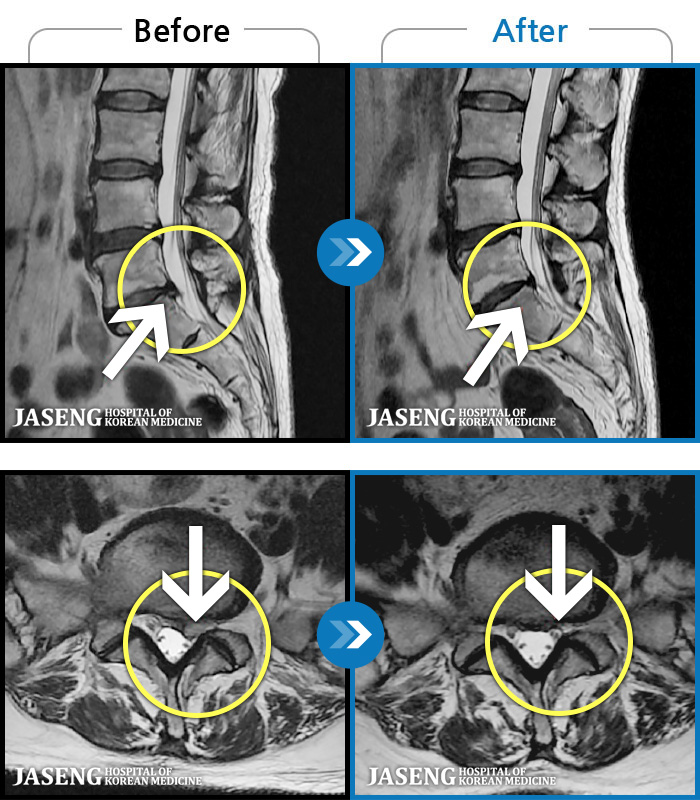

ȯںп Ǹ ǿ ԿǾ, ο ġ ۿ Ƿ ġḦ Ͻñ ٶϴ.